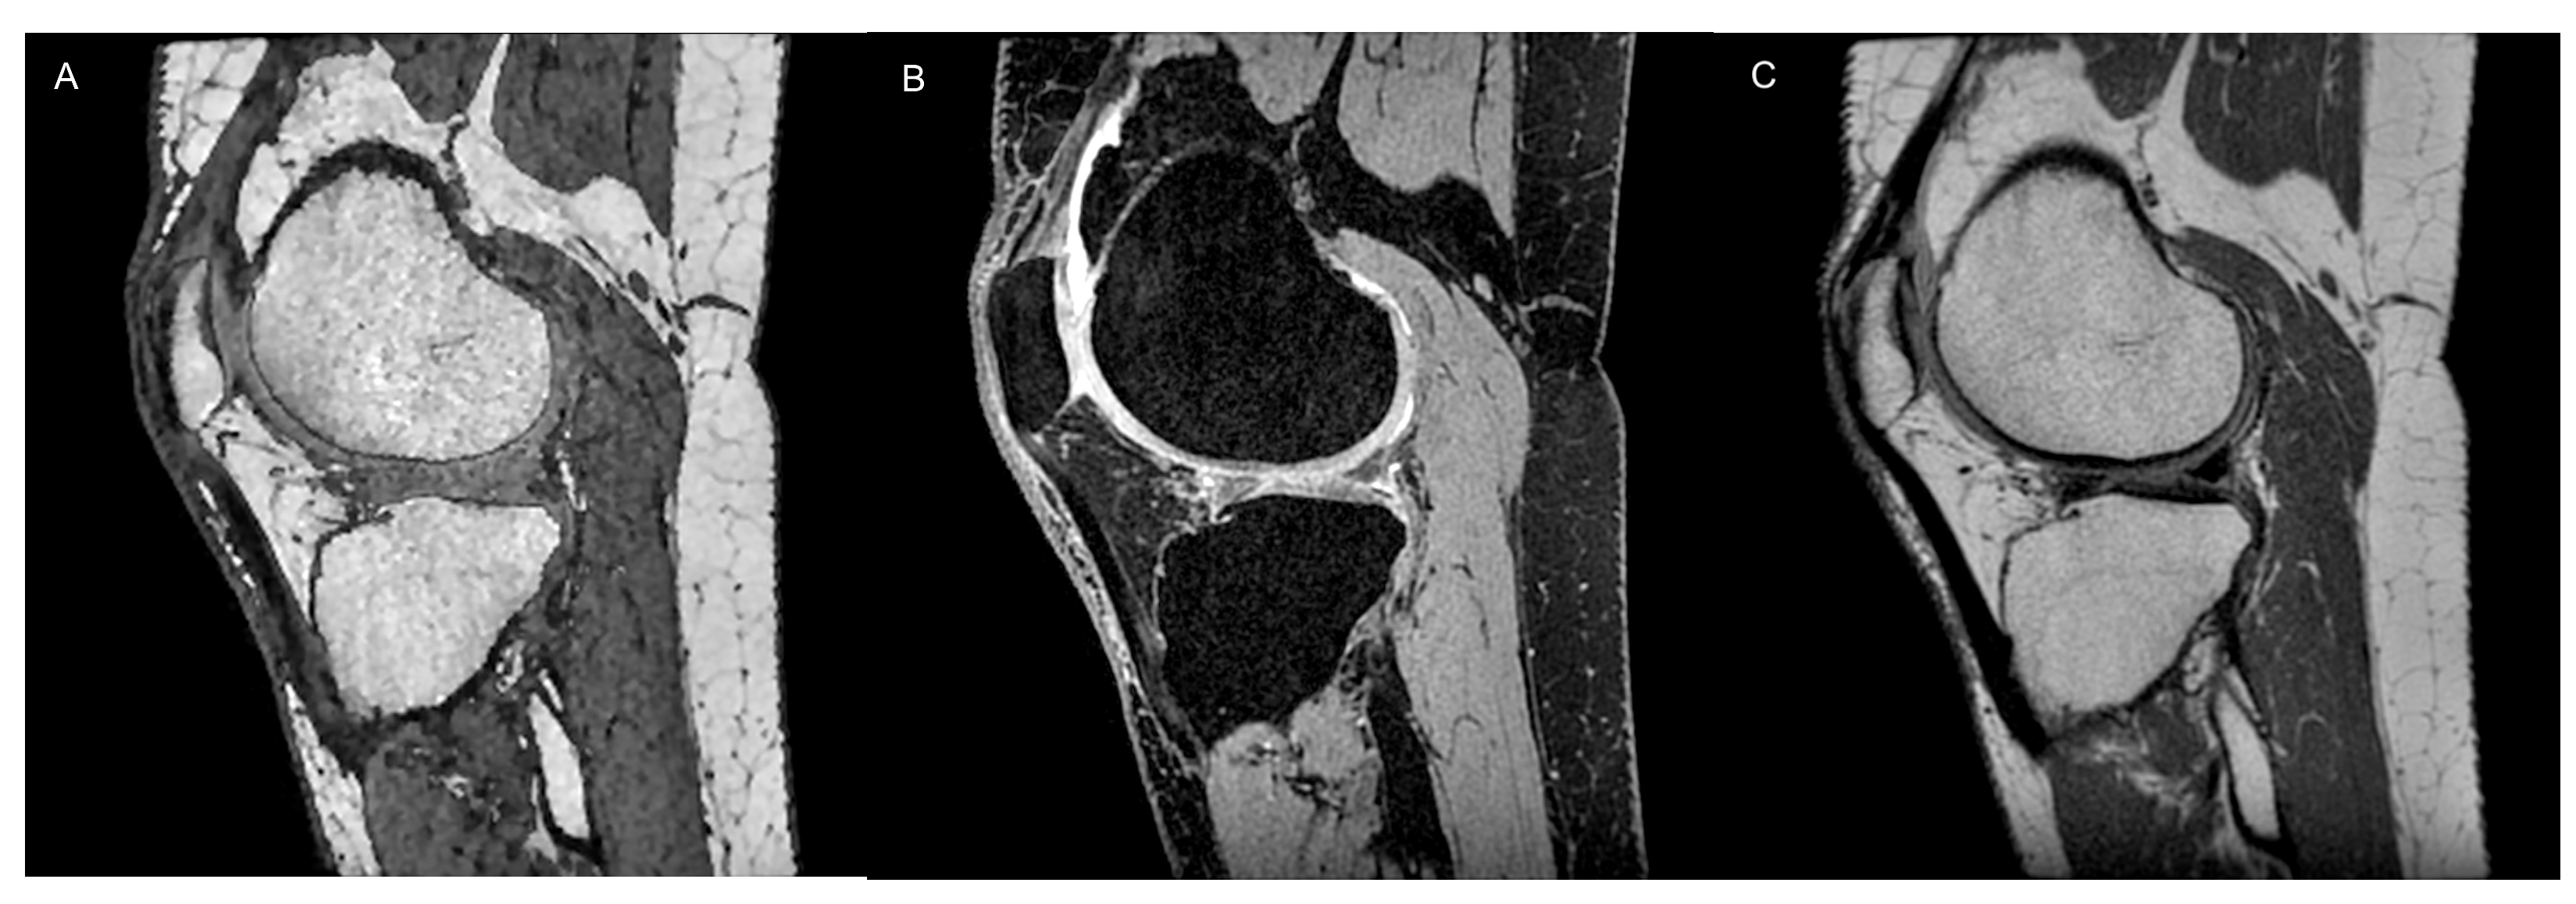

2.1. Conventional MRI

- Yang, X.; Li, Z.; Cao, Y.; Xu, Y.; Wang, H.; Wen, L.; Meng, Z.; Liu, H.; Wang, R.; Li, X. Efficacy of magnetic resonance imaging with an SPGR sequence for the early evaluation of knee cartilage degeneration and the relationship between cartilage and other tissues. J. Orthop. Surg. Res. 2019, 14, 152. [Google Scholar] [CrossRef] [PubMed]

- Kijowski, R. 3D MRI of Articular Cartilage. Semin. Musculoskelet. Radiol. 2021, 25, 397–408. [Google Scholar] [CrossRef]